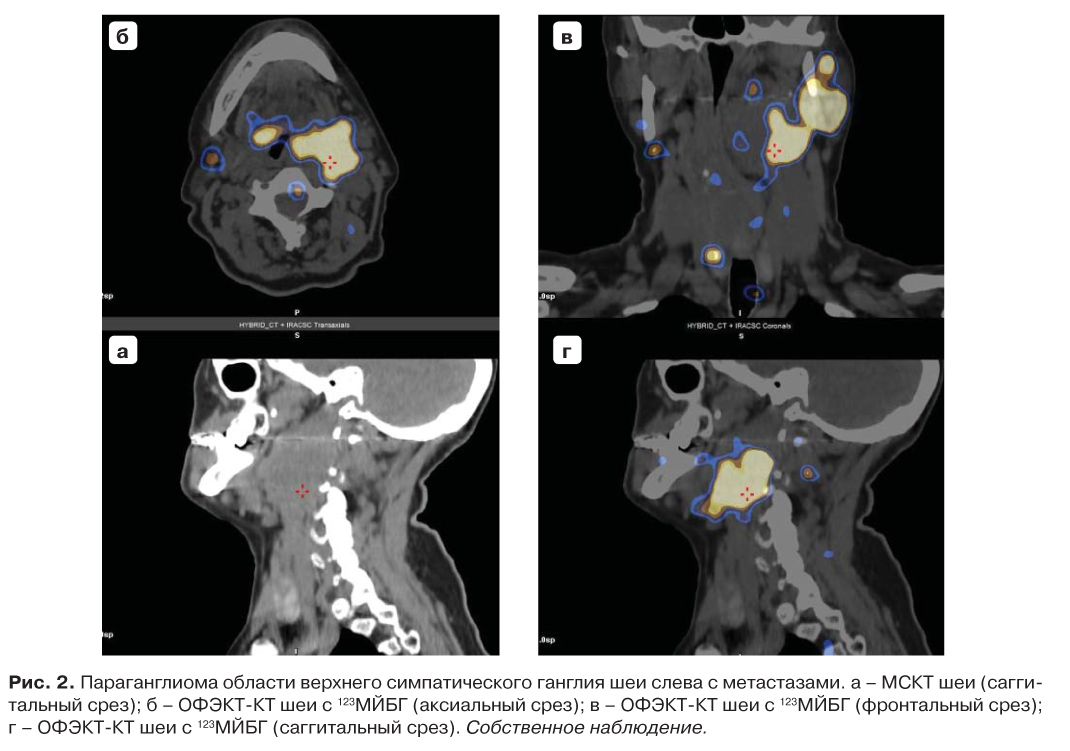

Для топической молекулярной визуализации параганглиом и феохромоцитом используется ОФЭКТ/КТ с 123I-МЙБГ. На рис. 1 демонстрируется собственный клинический случай феохромоцитомы левого надпочечника. На рис. 2 и 3 представленные собственные клинические случаи с локализацией опухоли на шее и в мочевом пузыре (встречается редко), соответственно.

Рис. 2. Параганглиома области верхнего симпатического ганглия шеи слева с метастазами. а – МСКТ шеи (сагги- тальный срез); б – ОФЭКТ-КТ шеи с 123МЙБГ (аксиальный срез); в – ОФЭКТ-КТ шеи с 123МЙБГ (фронтальный срез); г – ОФЭКТ-КТ шеи с 123МЙБГ (саггитальный срез). Собственное наблюдение.